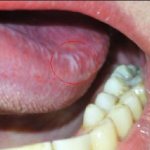

Эти симптомы стихают после возникновения пузырчатой бугристости в месте размножения возбудителя. Остроконечные кондиломы у женщин, фото которых поможет установить их размеры, могут составлять до 1-5 мм в диаметре и располагаться одиночно. Такие выросты почти не ощущаются. Возможен дискомфорт при ведении половой жизни. При увеличении размеров симптомы становятся более выраженными.

При локализации бородавок в ротовой полости возможно нарушение глотания, ощущение инородного тела.